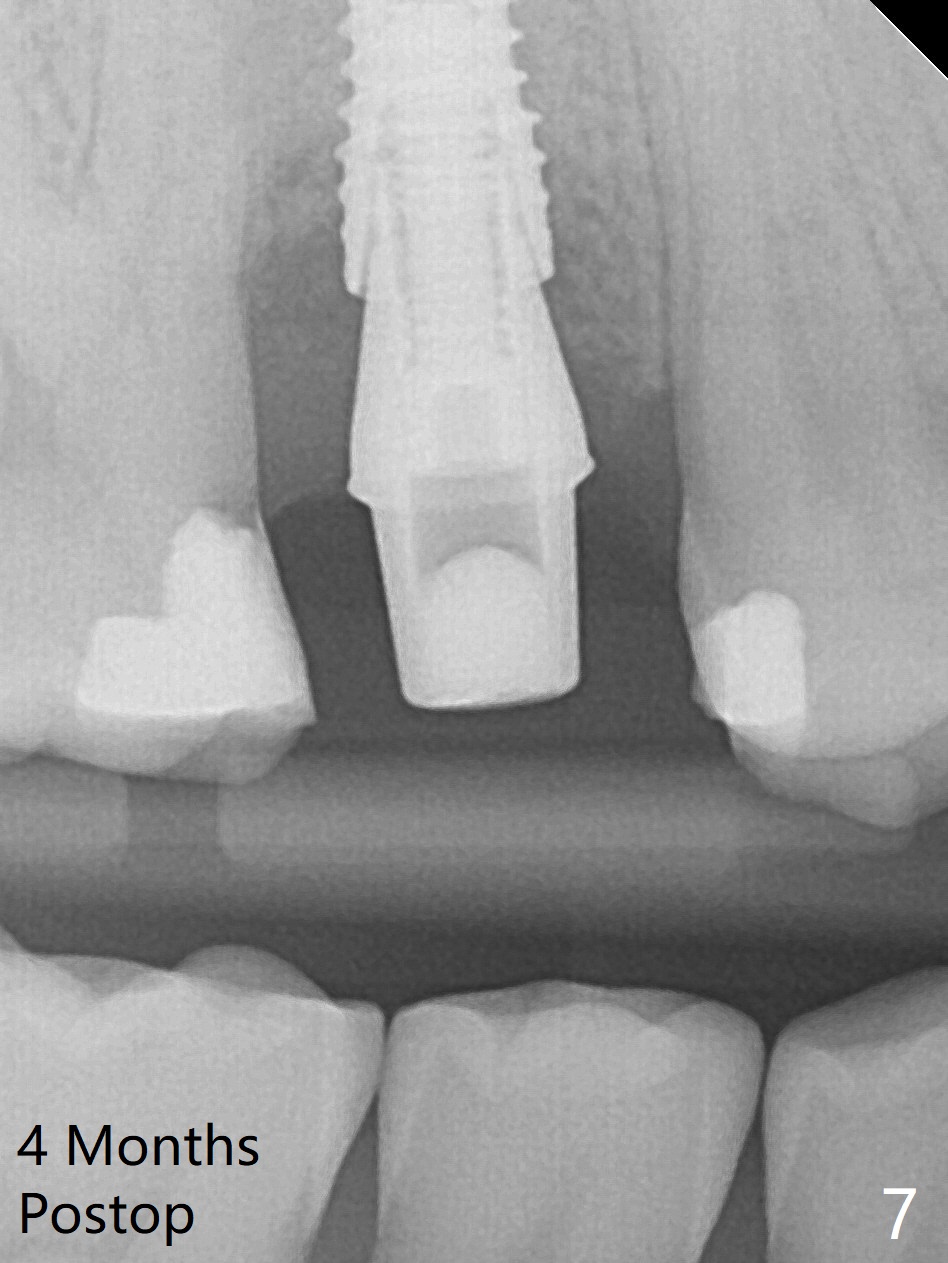

When the tooth #4 with vertical root fracture (Fig.1) is extracted, the buccal plate is found to be lost. The lowest point of the defect is shown as black dashed line in Fig.2 (yellow dashed line: sinus floor). After use of 2.5 mm reamer for 21 mm (buccal gingival level) and 3.0 mm reamer for ~17 mm, a 3.8x15 mm dummy implant is placed with 30 Ncm and 1.85 mm apical space (Fig.3 pink outline). A 3.8x18 mm (definitive) implant is placed with <40 Ncm with the implant plateau apical to the lingual crest (Fig.4,5). The buccal plate defect is repaired by Vanilla Graft (Fig.6 *) before and after insertion of a 4.5x4(3) mm abutment. The buccal plate defect seems to being repaired 4 months postop (Fig.7). Occlusal wear suggests bruxism, which is also associated with the root fracture. Night guard is recommended. The defect repair is close to completion 8 months post cementation (Fig.8). The crown/abutment is found to be loose 1 year 4 months post cementation and retightened without checking whether there is clinical 2nd DO caries of #3 (Fig.9, "sensitive to water pik"). A few days later, DO composite is being removed. It is difficult to determine whether the 2nd DO caries or gap has been removed with the neighboring crown in place. When the crown/abutment is removed and gingival retractions are inserted, there is no decay. The gap is removed. With Toflemire in place, the crown/abutment is reseated and hand tightened; after packable composite, the crown/abutment is removed, there is no more DO gap.